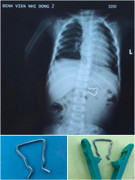

Một đoạn dây inox cong queo với nhiều cạnh sắc nằm gọn trong bụng bé trai 18 tháng tuổi được các bác sĩ Bệnh viện Nhi đồng 2 nội soi gắp ra thành công.